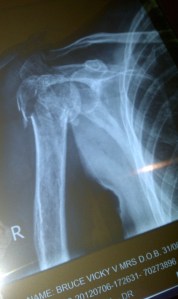

I felt like hitting my head against a wall! What did the child think? In 2007 Vic must have had 18 operations; developed every hospital superbug in the book; developed septicaemia, had a high output fistula; developed Acute Respiratory Distress Syndrome; spend months in ICU and survived having the ventilator turned off… Vic was op TPN (Total Parental Nutrition) for months…she had a massive open wound that we could not keep covered with a colostomy bag. It was too big and positioned very low down.

Vic in 2007